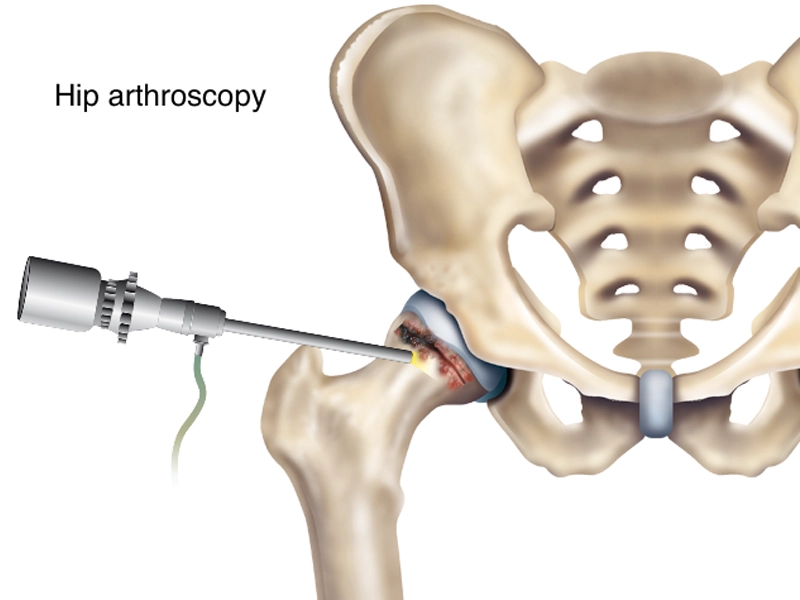

مراقبتهای بعد از آرتروسکوپی لگن برای دستیابی به بهترین نتایج و جلوگیری از عوارض ممکن، بسیار حائز اهمیت است. مراقبت های مناسب شامل مدیریت درد، فیزیوتراپی، محدود کردن فعالیتهای فیزیکی در مراحل اولیه بهبودی و انجام تمرینات خاص برای بازگرداندن دامنه حرکتی مفصل هستند. این مراقبتها نه تنها به تسریع روند بهبودی کمک میکنند، بلکه […]